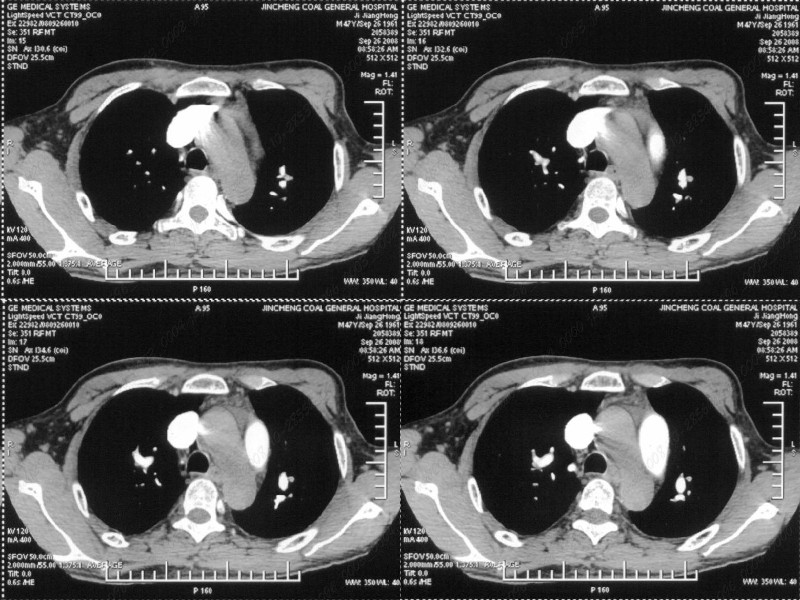

男性,47岁。胸部不适一年,ct检查发现右胸膜下结节。http://www.radida.com/bbs/forum.php?mod=viewthread&tid=46094

图像很清,资料很全。工作做的很细,向您学习!观阁下的强化图像发现,您们强化后扫描时间挺早,延迟时间大约在16—18秒之间吧。估计目的是为了观察肺动脉及分支的情况。但现有的资料并不能提示动脉栓塞改变。建议楼主可在机器上仔细观察,或许会有异常发现。另外,个人感觉右侧应为肺内结节而非胸膜结节。考虑肺内良性小结节,炎性假瘤可能性大。

病灶周围似有纤维化征像,增强明显强化,但中央可见点状低强化区,考虑慢性病变可能如炎性假瘤等,病灶边缘部分毛糙有切迹,双侧胸腔少量积液影,不除外恶性

结节未见明显强化,局部胸膜增后粘连,内缘纹理影增重伴小围星灶,局部胸膜下小三角状实变影,尖端见纤维索牵扯征,综合考虑炎性病变,有增殖表现,不出外tb灶

右肺中叶外侧段胸膜下结节状病灶,性质待定(不排除周围型肺癌可能)。